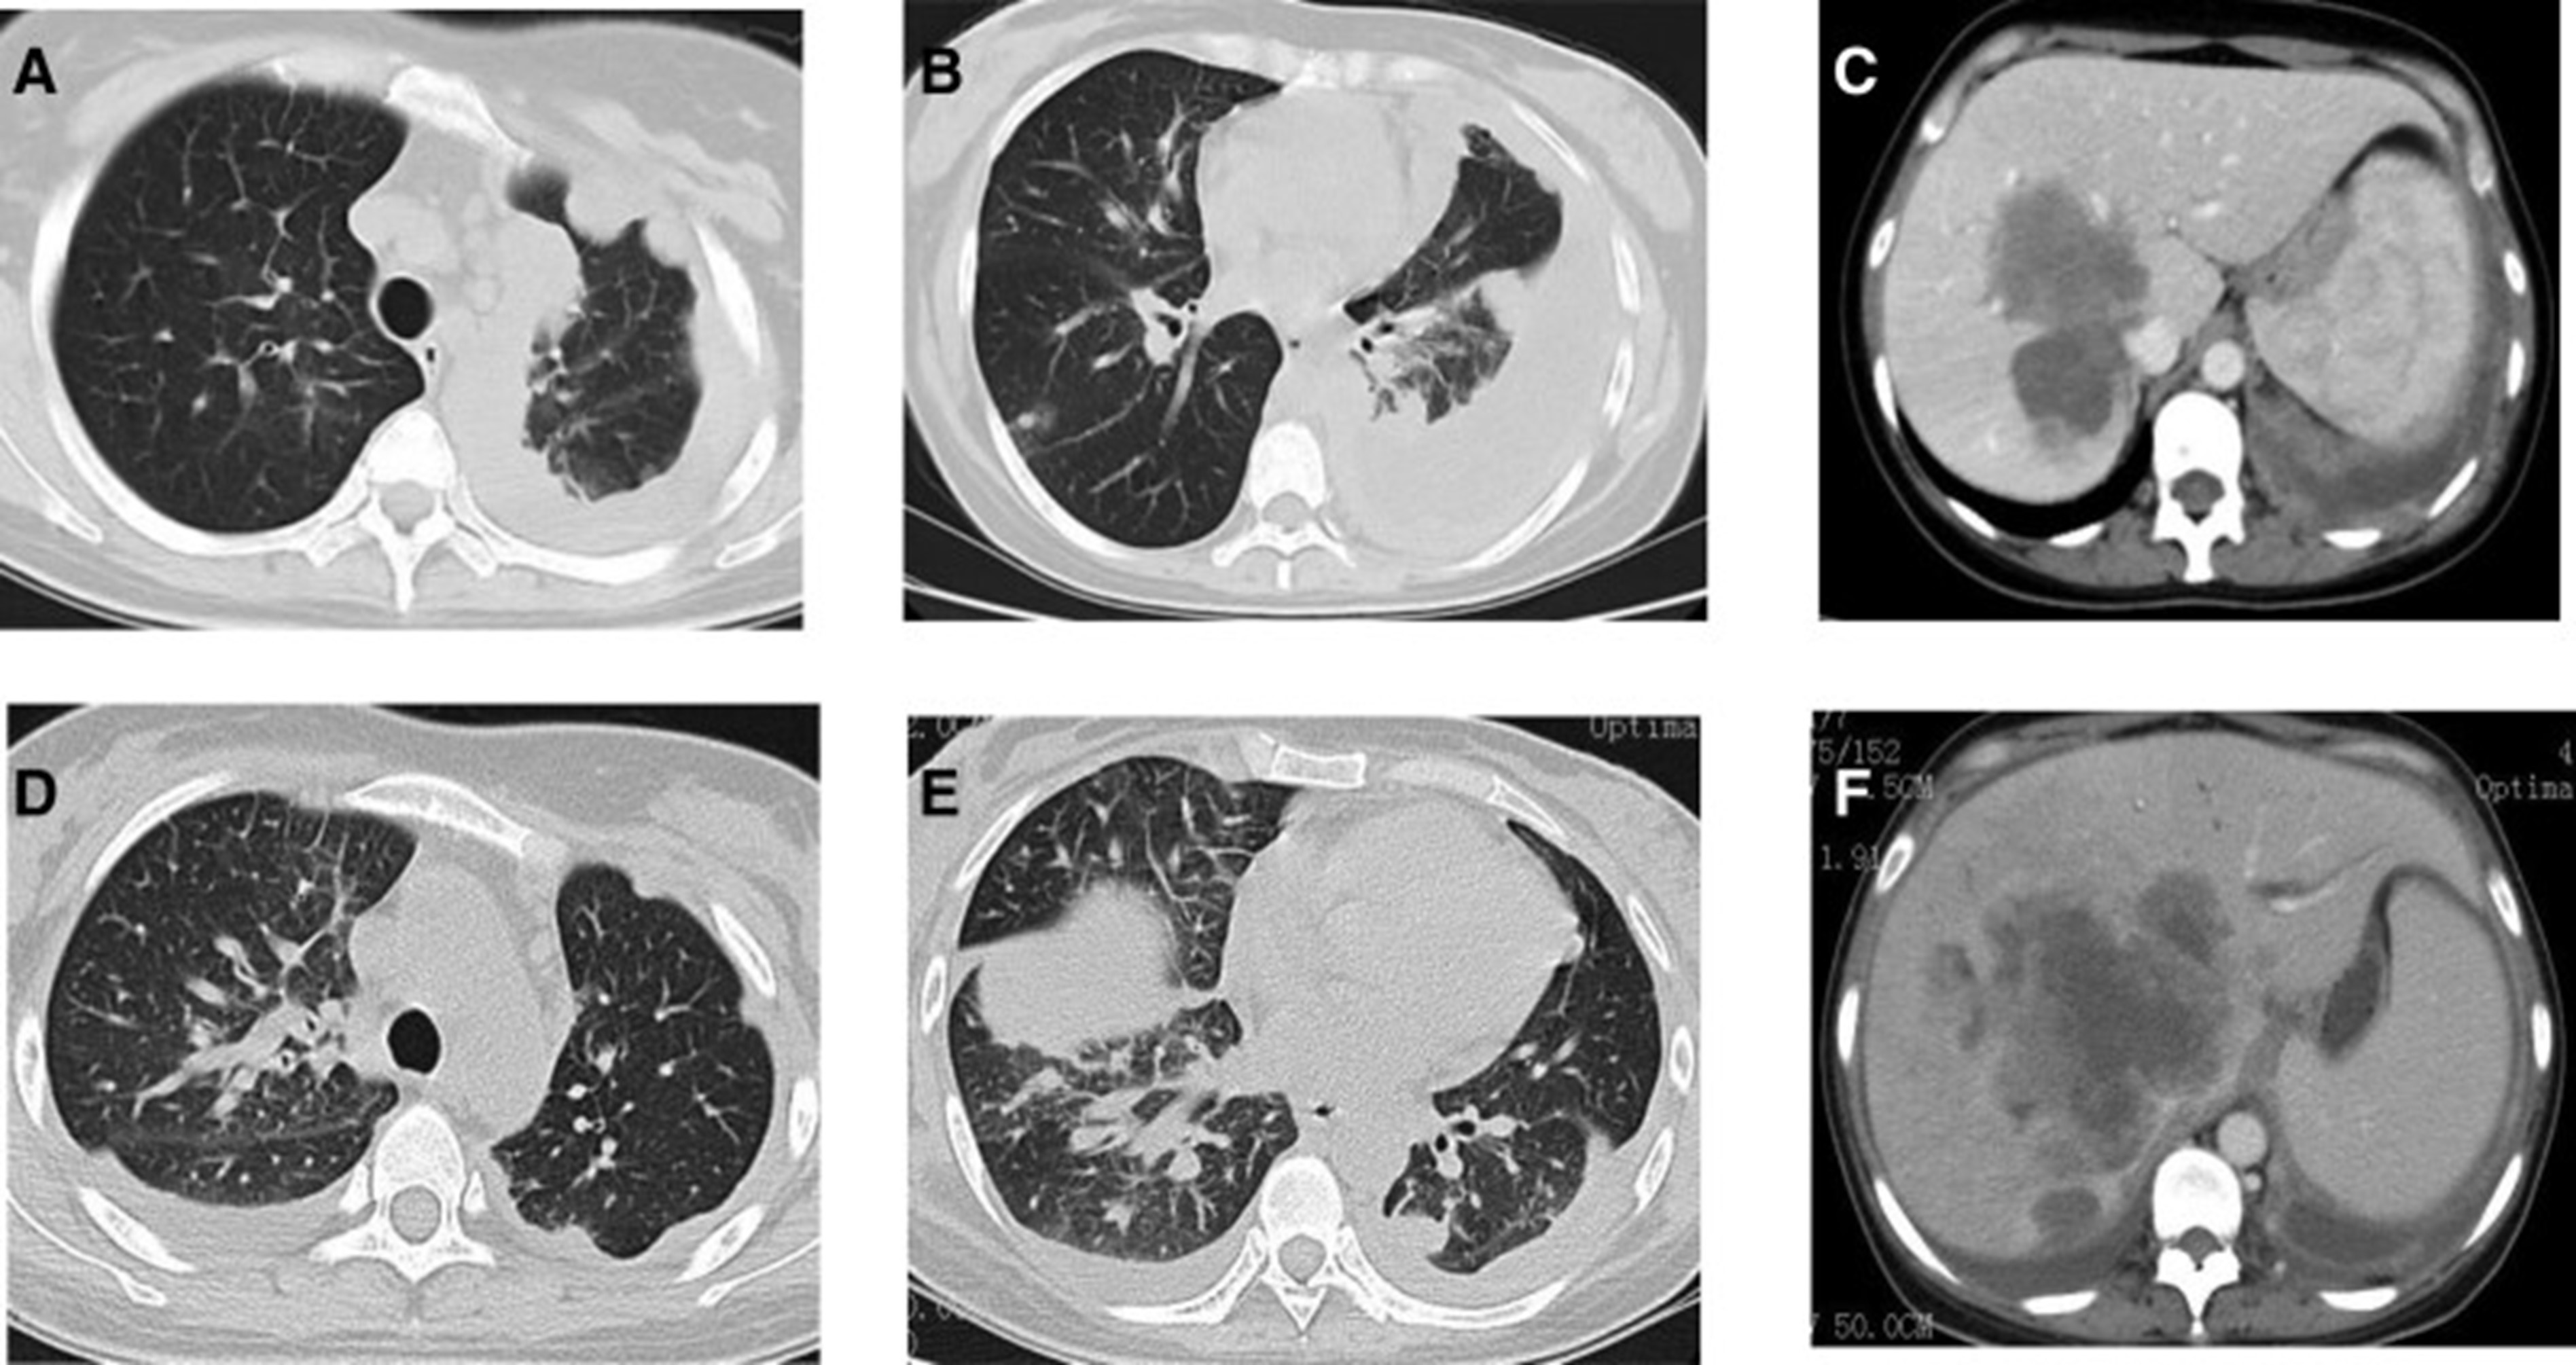

2020年4月,患者胸部CT示“双肺多发结节,纵隔及肺门多发肿大淋巴结;附着于肝右叶,略呈低密度肿块影”(图 1)。(图4A,4A、B)和腹部CT显示“肝脏多发肿块”(图1)。(图 4C)。骨扫描显示“身体多个部位的骨代谢异常增强”。2020年4月19日,对“右肝肿块和右锁骨上肿块”进行活检,病理指征(右肝肿块抽吸、右锁骨上肿块抽吸)为低分化腺癌。结合免疫组化结果,首先考虑的是肺腺癌转移。最终诊断为“IV期肺腺癌伴多发肝和骨转移”。基因检测显示“EML 4-ALK 融合,PD-L1 肿瘤阳性细胞数TPS 80%”(图 2)。(图1和和2)。

和 2020 年 6 月 (D-F).jpg)

图 4:2020 年 4 月 (A-C) 和 2020 年 6 月 (D-F) 的 CT 扫描。CT = 计算机断层扫描。

2020年5月1日,患者开始口服艾乐替尼靶向药物进行治疗,2020年6月25日复查,确定治疗效果为PR(部分有效)(根据RECIST1.1)显示肺病灶和肝转移灶明显减少(图1)。(图 3D-F)。2020 年 8 月 27 日复查确定治疗效果为疾病进展(PD, progressive disease),根据 RECIST1.1显示肝脏病变变大(图 1)(图 4A-D)。进行了第二次肝活检,随后的病理学显示“(肝)低分化癌,结合免疫组织化学分析考虑肺腺癌转移”。组织活检进行了第二轮基因检测,结果显示“BRAFV600E 14.79%,EML 4-ALK fusion 14.47%”(图 1)(图 5)。2020年9月20日,对患者我以为用恩沙替尼联合达拉非尼靶向治疗。治疗开始后,患者出现明显发热、寒战、乏力和厌食。期间患者左侧出现大量胸腔积液,胸腔积液中脱落细胞为“非典型细胞,考虑为腺癌”。随后,该患者接受了 1 次胸腔内铂输注。

和 2020 年 8 月.jpg)

图 5:2020 年 6 月(A 和 B)和 2020 年 8 月(C 和 D)的 CT 扫描。CT = 计算机断层扫描。

1个月后复查显示肺部和肝内病变进展(图1)。(图 6A-C)(根据RECIST1.1),她的抗肿瘤治疗改为“培姆曲塞加卡铂和贝伐单抗”的治疗一个周期。2020年12月至2021年1月,再次改变患者的治疗方案,这次改为“劳拉替尼联合达拉非尼”靶向治疗。使用 PD 联合胸部和腹部 CT 评估疗效(图 1)。(图 6D-F)(根据 RECIST1.1)。患者无法耐受化疗、靶向治疗、IO 治疗或任何其他积极的抗肿瘤治疗。这是因为患者的一般情况较差,包括发烧、腹痛和胆红素水平升高等症状。随后,给予患者静脉营养、镇痛等对症支持治疗。患者于 2021 年 2 月 4 日去世,总生存期(OS)为 10 个月。

和 2022 年 1 月 (D-F) 的 CT 扫描.jpg)

图 6:2020 年 11 月 (A-C) 和 2022 年 1 月 (D-F) 的 CT 扫描。CT = 计算机断层扫描。